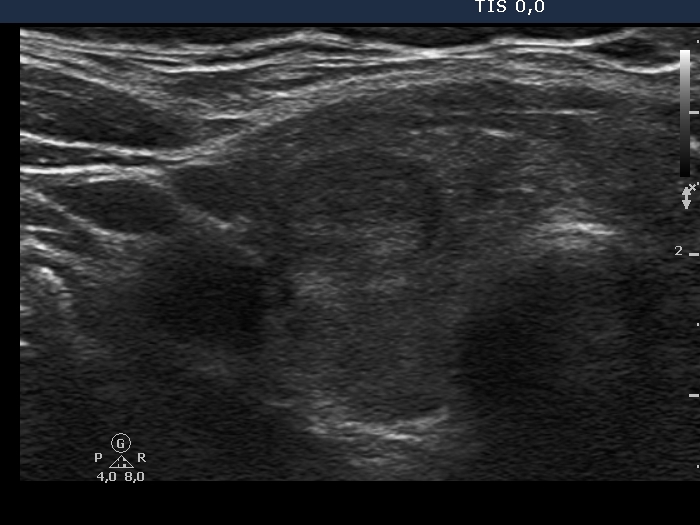

Examination in 2013 (first row of images):

Clinical data. A 50-year-old woman was referred for evaluation of a nodular goiter. The patient has been treated for hypothyroidism for 16 years.

Palpation: Both lobes were a bit firm, no nodule was palpable.

Laboratory test: TSH 4.01 mIU/L on daily 100 microgram levothyroxine.

Ultrasonography. The thyroid was minimally/moderately hypoechoic and had several discrete minimally/moderately hypoechoic lesions.

Cytology was performed from the lesion in the central part of the right lobe and resulted in Hashimoto's thyroiditis.